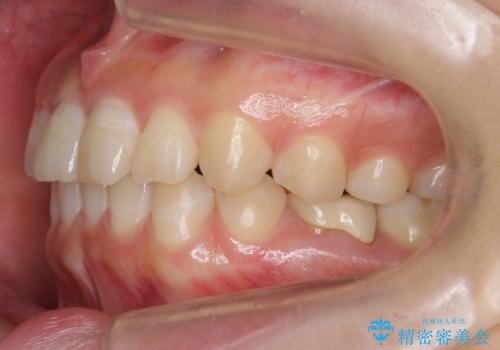

左下に乳歯が残っていましたが、被せ物に穴が空いている状態でした。

乳歯は抜かずに保存的な治療を行いました。

上下の正中が1本分ずれていましたが、ちょうど1本分で目立たず、また、右下の歯が生まれつき少ないことを利用して、最小限の歯の移動にとどめました。

乳歯はまだぐらついたりしていない状態だったため、しっかり虫歯を取り、根の治療も行いました。